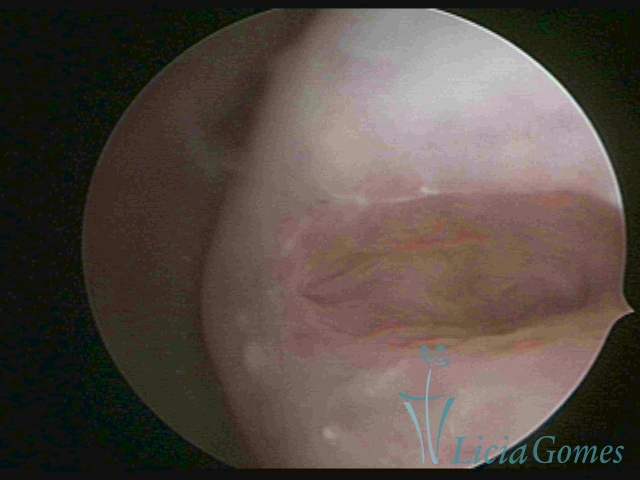

First part or proximal section or lower section:

During the proliferative phase, a light, crystalline mucus with a low adherence to the scope is found. The crypts and buds are a little swelled and vascularized, microvesicular, resembling grape clusters.